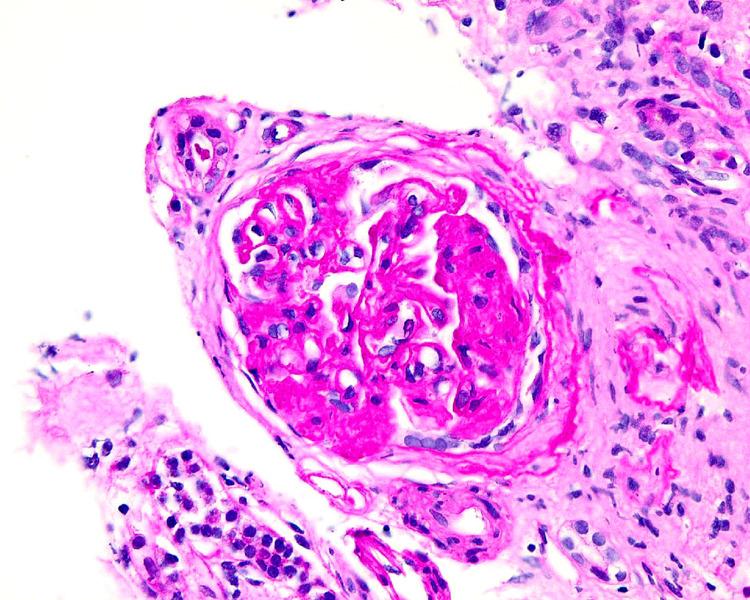

丙型肝炎相关塌陷性肾小球病继发急性肾衰竭和肾病综合征

Acute Renal Failure and Nephrotic Syndrome Secondary to Collapsing Glomerulopathy Associated With Hepatitis C.

Collapsing glomerulopathy (CG) is a rare variant of focal segmental glomerulosclerosis (FSGS) that commonly presents as nephrotic syndrome in patients. CG is almost always associated with human immunodeficiency virus (HIV) infection but is rarely from other infectious sources such as parvovirus, Epstein-Barr virus, cytomegalovirus, and SARS-CoV-2. CG has also been reported to be related to other etiologies such as genetic disorders, lupus, malignancy, and post-renal transplant but is exceedingly rare when related to hepatitis C virus (HCV). In this report, we describe the case of a patient presenting with nephrotic syndrome secondary to CG caused by newly diagnosed HCV.

摘要

塌陷性肾小球病(CG)是局灶节段性肾小球硬化(FSGS)的一种罕见变体,通常在患者中表现为肾病综合征。CG几乎总是与人类免疫缺陷病毒(HIV)感染相关,但很少源于其他感染源,如细小病毒、爱泼斯坦-巴尔病毒、巨细胞病毒和严重急性呼吸综合征冠状病毒2(SARS-CoV-2)。CG也被报道与其他病因有关,如遗传疾病、狼疮、恶性肿瘤和肾移植后,但与丙型肝炎病毒(HCV)相关时极为罕见。在本报告中,我们描述了一例因新诊断的HCV导致CG继发肾病综合征的患者病例。